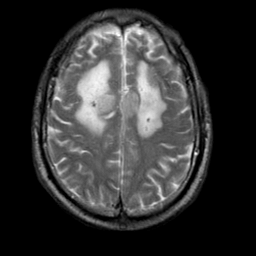

Meningioma, MR Study #2 -- Slice #14

[Home][Help][Clinical] Slice 14